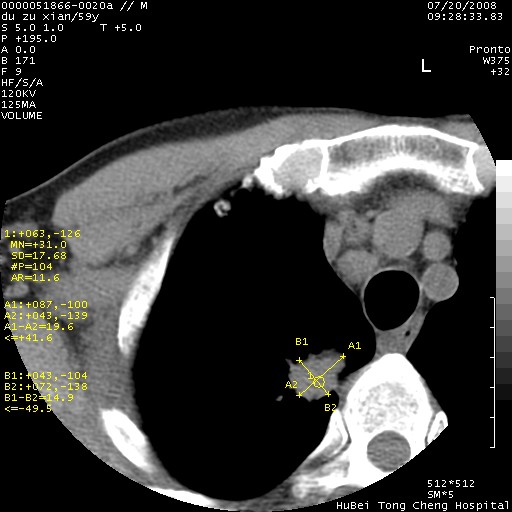

以下是引用宇宙ct在2008-8-25 23:21:00的发言:[br]右肺周围性肺癌并肋骨转移,纵隔淋巴结转移。

以下是引用zsl6918在2008-8-25 22:40:00的发言:[br]右肺周围性肺癌并肋骨转移,纵隔淋巴结转移。

以下是引用zy_zj在2008-8-26 15:24:00的发言:[br]单从病变本身,我倾向良性炎性病变,但肋骨转移了,所以说是考虑右肺周围性肺癌并肋骨、纵隔淋巴结转移可能性大。